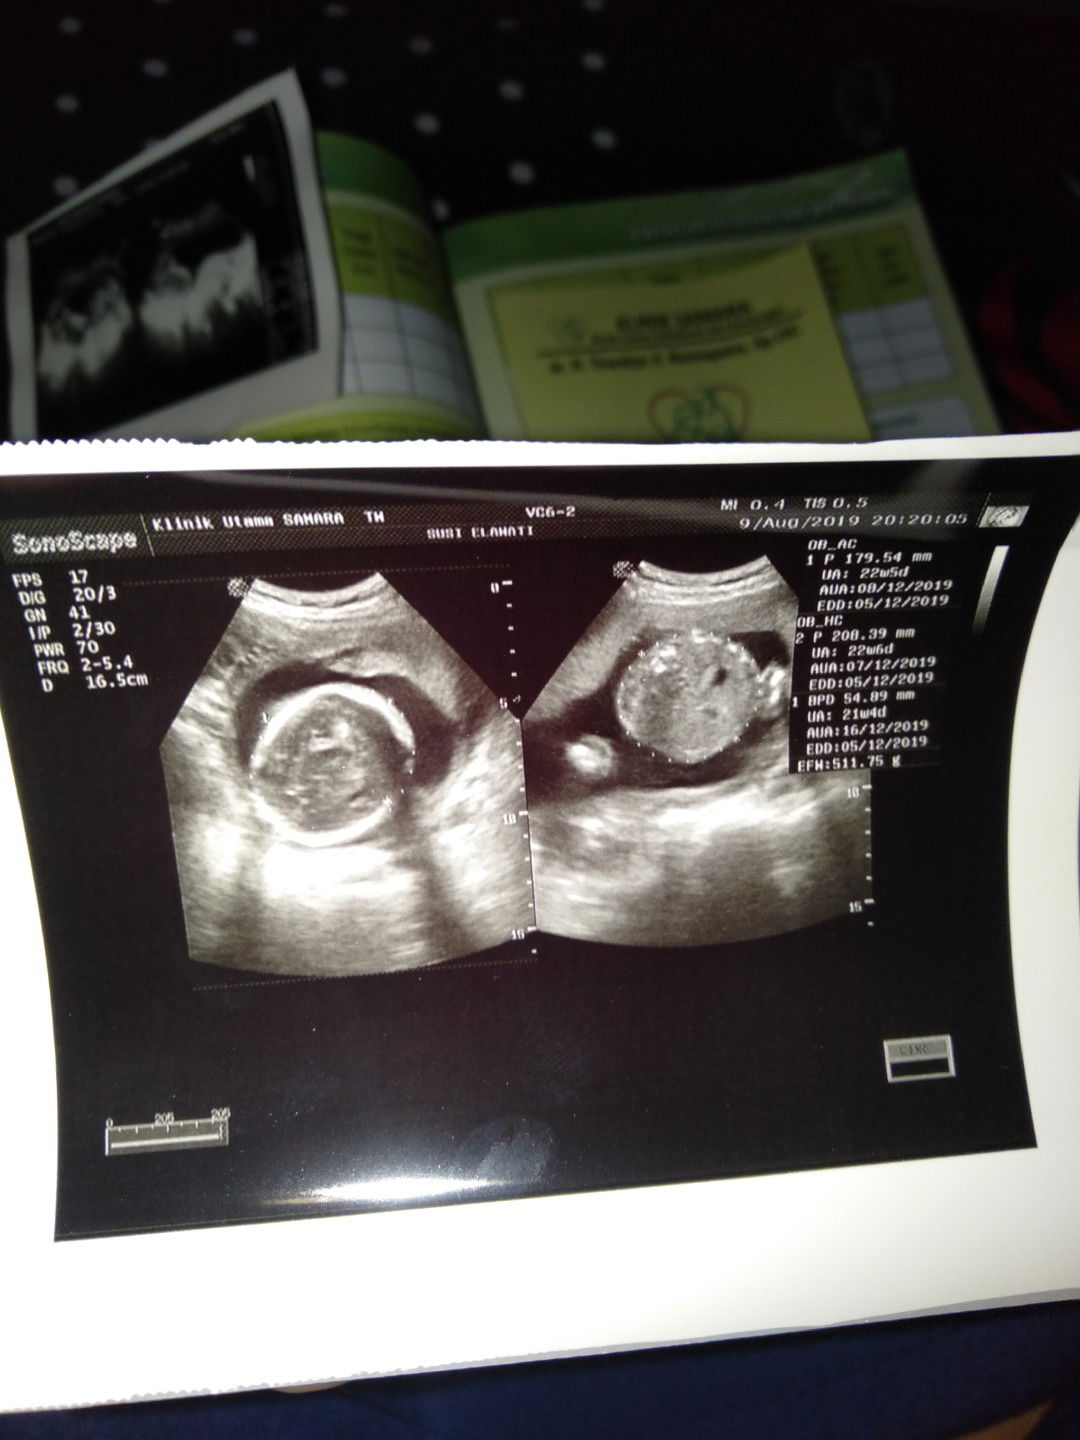

BB janin kurang

Bun makanan apa ya yang cepet buat nambahin BB janin di usia 22 week?